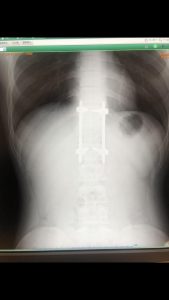

胸椎・腰椎脱臼骨折のリハビリトレーニング